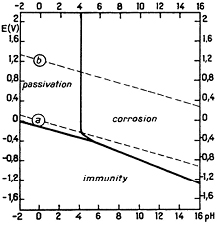

According to Pourbaix, the borderline conditions of corrosion/passivation occur between pH 4–6 (figure 1). Above pH 6, general corrosion will occur, with hydrogen evolution in the absence of oxidising species, and without hydrogen evolution in their presence. The tendency for corrosion rises with increasing potential [19], as may occur when W is used as stimulating electrodes. Weidman reports that at current densities exceeding 0.1 mA cm−2 there is a breakdown in the passivated surface regardless of pH, even in acidic zones [22]—a possible alteration to Pourbaix's initial diagram. This acid-soluble  ion has been proposed by others [43, 44].

Figure 1. Pourbaix's theoretical EH/pH diagram for W in H2O at 25 °C [20].

Standard image High-resolution imageThe original Pourbaix diagram applies to pure water at 25 °C, not the physiological environment, and thus should be used with caution. His analysis also ignores the numerous complexes W forms—these include hydrochloric complexes of trivalent W, hydrofluoric and oxalic complexes of tetravalent W, and cyanide complexes of pentavalent W. Some tungstates of alkali metals are soluble, while others are not [45].

A useful improvement to the diagram was generated computationally by Patrick for W in phosphate-buffered saline (PBS) using the CorrosionAnalyzer 1.3 software—approximately 60 solid, aqueous, and gaseous species were considered [13]. It is redrawn here for clarity with dominant species labelled (figure 2). Similar conclusions can be made: W is clearly a base metal, with a stable domain in the physiological pH range (x–y) (5.6 to 9.0 [14]) only outside of the water window (a–b).

Figure 2. EH/pH Diagram for W in PBS based on Patrick's work [13].